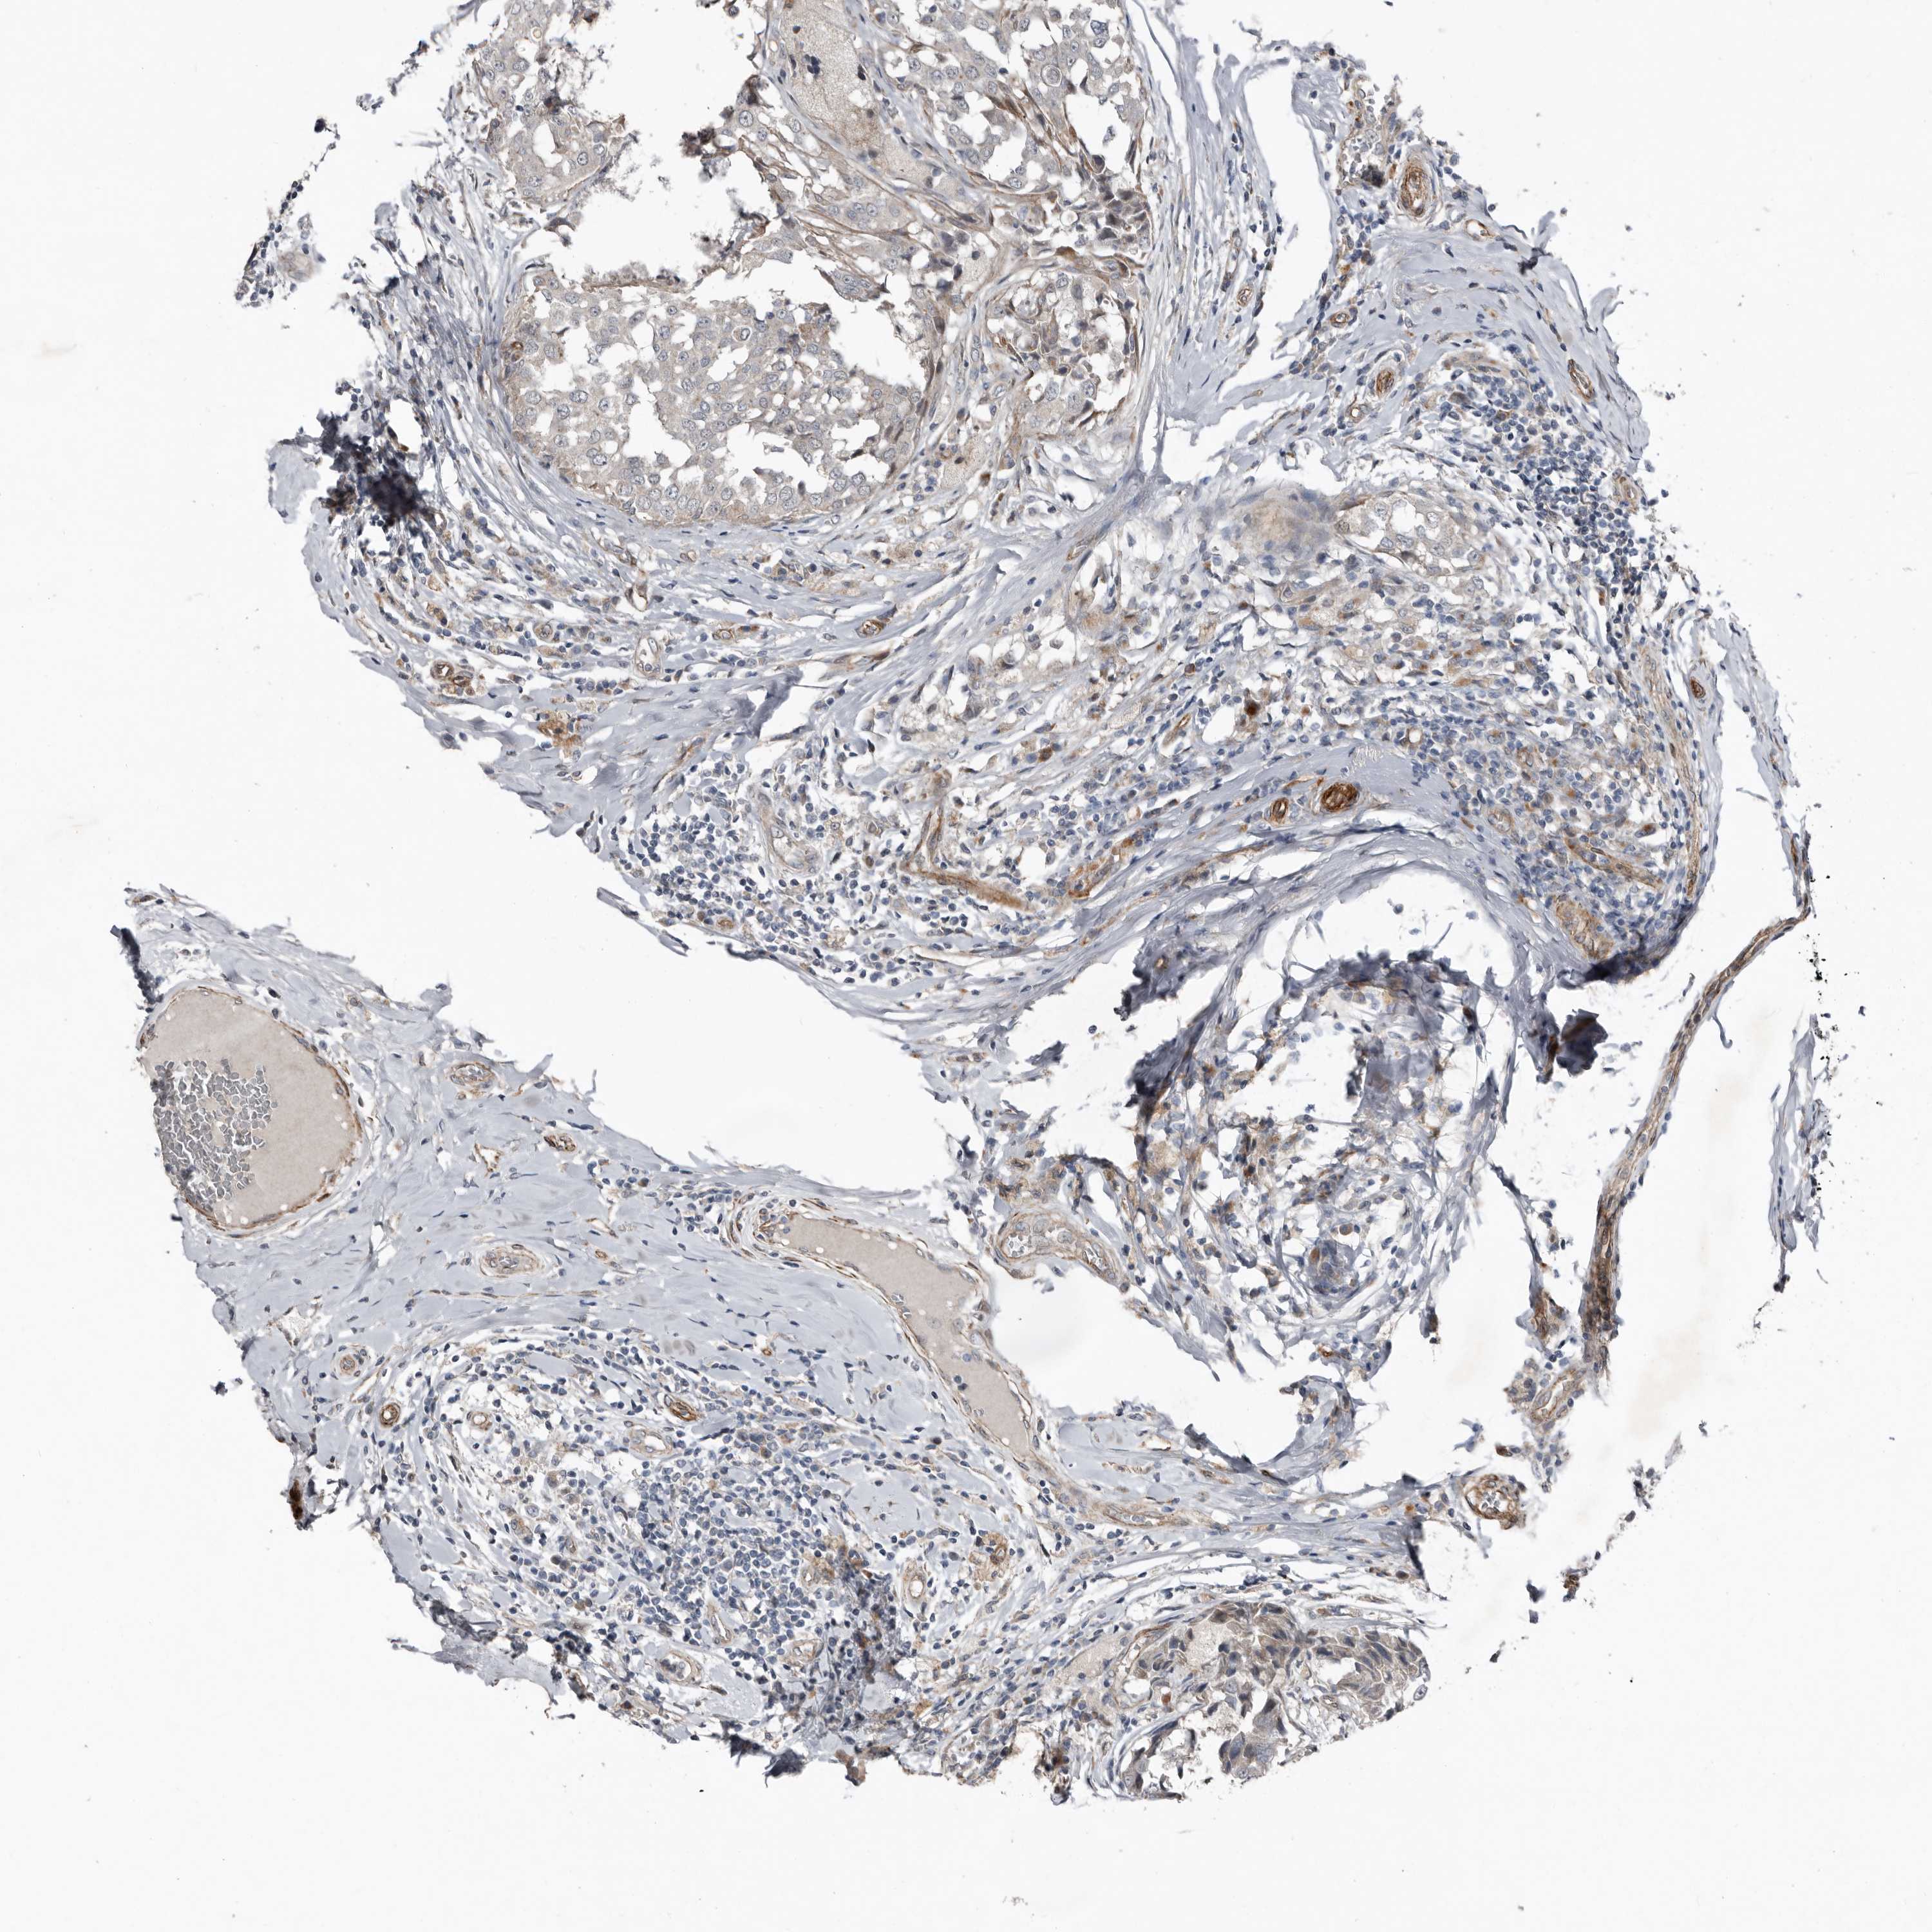

CANCER BREAST CANCER Show tissue menu

BRCA TCGA BRCA VALIDATION PROTEIN EXPRESSION